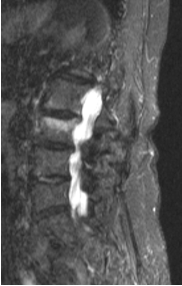

T1 weighted (T1W) image: TR and TE are short. (TR = 700 ms, TE = 20 ms). Characteristic signal intensities: water is mild, fat is very intense, muscle is medium intense, flowing blood has no signal (black).

- T1W image: (brain, sagitta slice, arachnid cyst)

- T1W image + iv. contrast material (enhancement is seen in the right ponto-cerebellar angle: Schwannoma.)